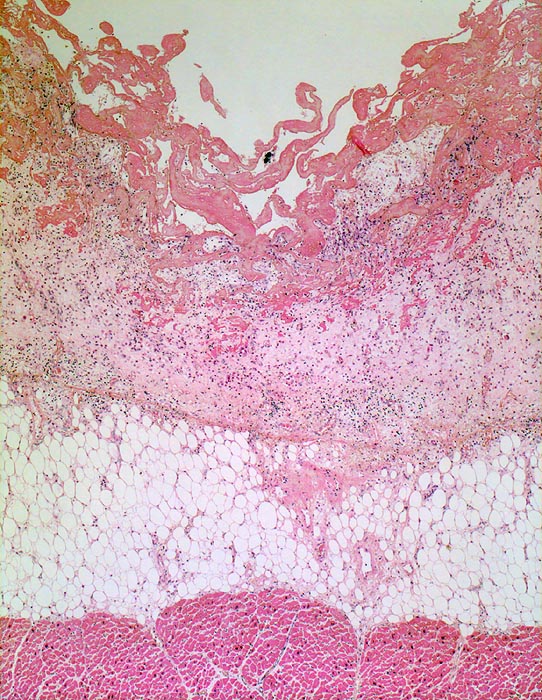

PathoPic ID 4532 - fibrinöse Perikarditis

fibrinöse Perikarditis

Entzündung / Reparatur

Perikard

Körperhöhlen, Serosa

Das Epikard bedeckt von

Fibrin. Das Fibrin wird von

Granulationsgewebe organisiert.

Epikardiales Fettgewebe und

Myokard.

Patientin verstorben in Urämie.

Nach Abschluss der Organisation bleiben fibröse Perikardverwachsungen zurück (Narbe).

Histologie

25